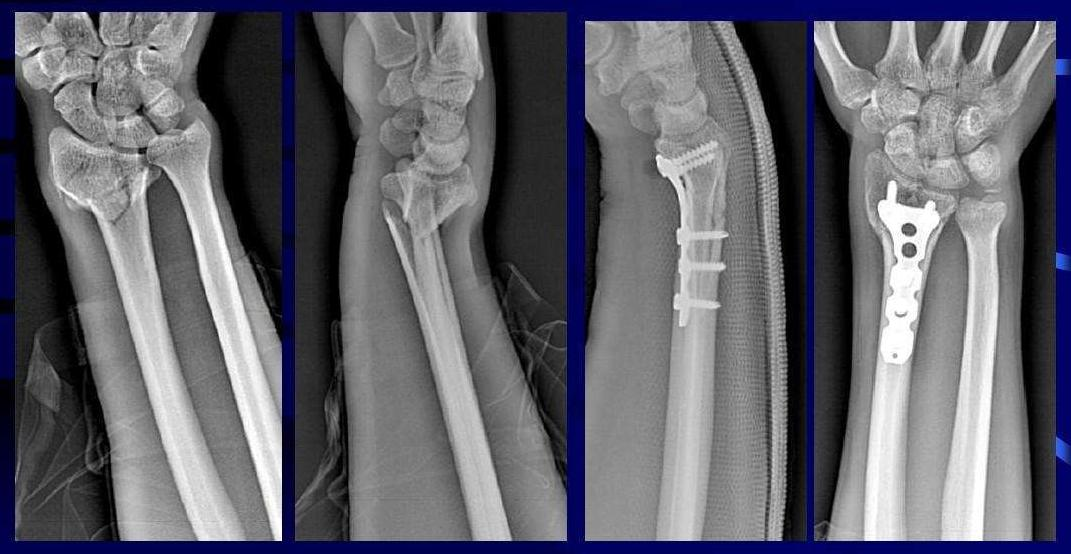

謝先生今年32歲,在工作時不幸遭遇車禍,導致左橈骨遠端骨折,在外院做了左橈骨骨折切開復位內(nèi)固定術,病情平穩(wěn)后回家療養(yǎng),但仍感覺疼痛、腫脹明顯,左手活動障礙,左手失去自理能力。為進一步減輕疼痛,改善運動功能,來到惠州三院骨科康復科行康復治療。醫(yī)生查體發(fā)現(xiàn),患者左前臂、左腕、手指腫脹;左腕周圍肌肉皮溫較右側皮溫高;左前臂旋轉、左腕屈伸、左腕尺偏橈偏、左手指活動明顯受限;VAS:4分。

康復技師介紹,橈骨骨折患者經(jīng)過手術治療,石膏外固定制動,損傷的軟組織、肌肉及骨折愈合過程中,肌肉、肌腱之間難免存在粘連,骨折新形成不規(guī)則骨贅,上述情況容易導致手的僵硬、活動障礙。

初入院時→治療2周后